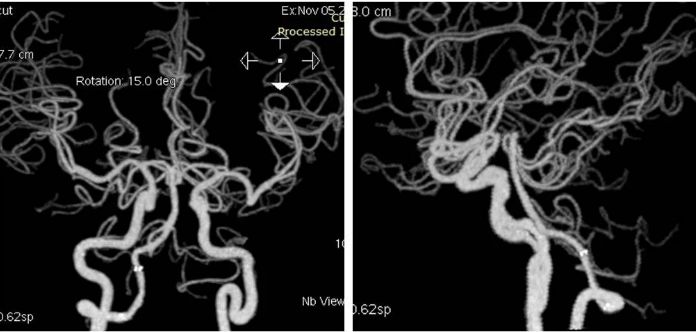

头部CTA+CTP:右椎动脉V4段长段重度狭窄,左椎动脉V3段闭塞,基底动脉近端见开窗(图5);后循环分布区低灌注(图6)。

图5

其后送入XT-27微导管,释放Neuroform EZ (4.0mm x 20mm )自膨式支架,造影提示支架释放后支架贴壁良好,前向血流TICI 3级(图10)。

图10

术后复查头颅CTA:右椎动脉V4段支架内通畅(图12)。

图12